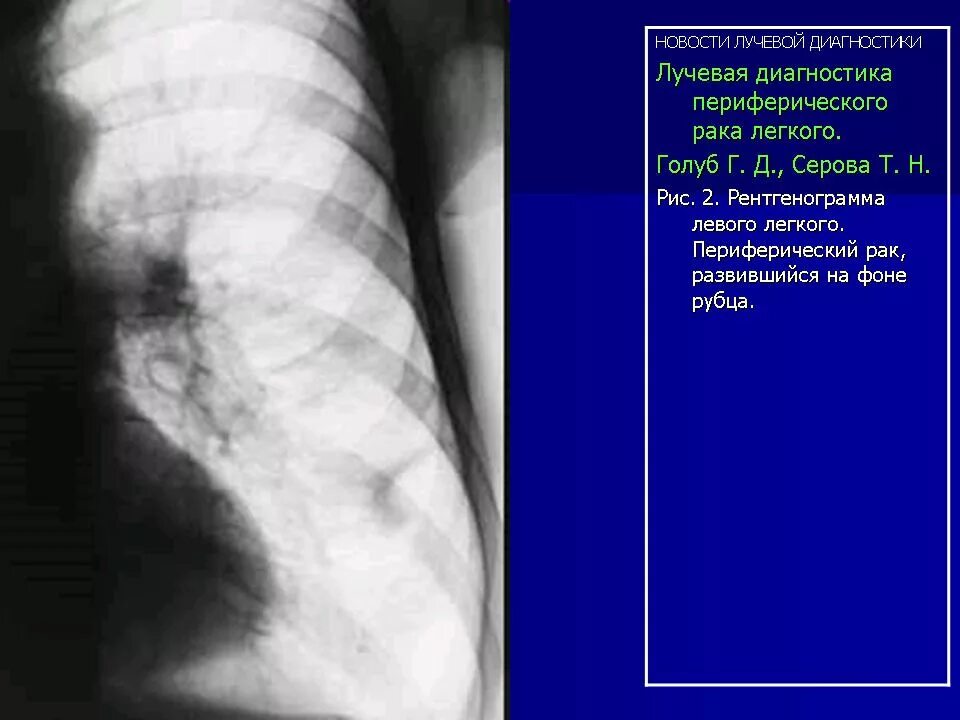

Лучевая при раке легких